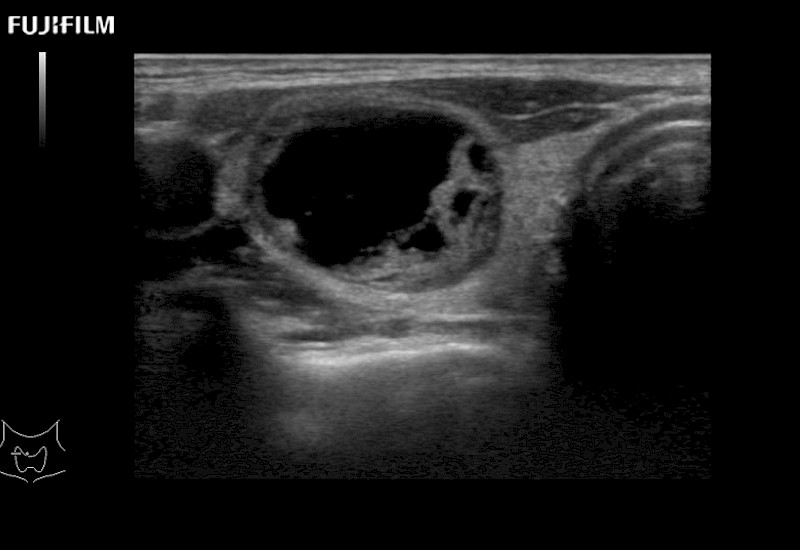

Curved array deep penetration “T” style finger-grip transducer for open surgical procedures.